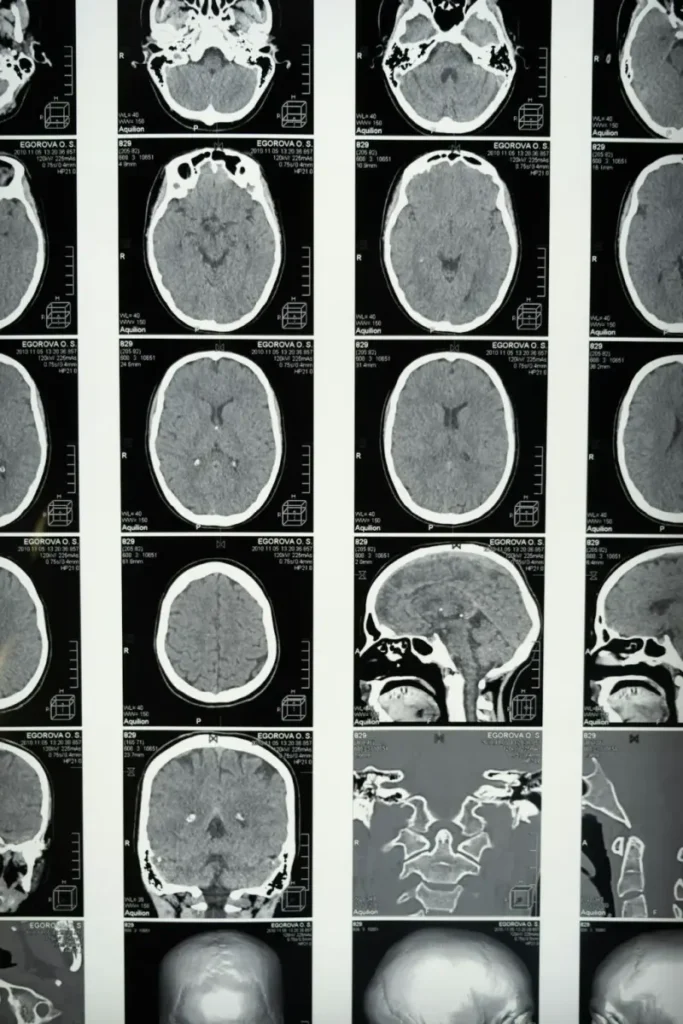

Magnetic resonance imaging, czyli rezonans magnetyczny, to jedno z najchętniej wykorzystywanych badań diagnostycznych w obecnych czasach. Nie można obawiać się tego badania, ponieważ jest ono bezbolesne. To właśnie dzięki niemu lekarz może zajrzeć w głąb ciała, dzięki czemu możliwe będzie postawienie trafnej diagnozy. Oto garść niezbędnych informacji, które mogą przydać się tym osobom, jakie przygotowują się do rezonansu magnetycznego. Czy na MRI można zdecydować się samodzielnie?

Badanie rezonansem magnetycznym

Z reguły nie trzeba specjalnie przygotować się do tego badania. Aczkolwiek, jeżeli u pacjenta podejrzewana jest zaburzona praca nerek, to na ok. tydzień przed badaniem warto zmierzyć poziom kreatyniny. O tym jednak decyduje lekarz. Samo badanie, jak już było wspomniane, jest bezbolesne i nie trzeba się niczego obawiać. Samo badanie może trwać kwadrans, ale także znacznie dłużej – prawie godzinę. Wszystko bowiem uzależnione jest od tego, jaki dokładnie obszar ciała zostaje sprawdzony. Należy pamiętać o tym, aby na ok. cztery do sześciu godzin przez badaniem nic nie jeść. Trzeba być na czczo. Dyskomfortem może być jedynie to, że w trakcie badania należy leżeć nieruchomo w wielkiej tubie. Nie można się poruszać. Pacjentowi (szczególnie małym dzieciom) może zostać podane znieczulenie, aby leżenie w jednej pozycji było możliwe. Nad pacjentem zawsze czuwa sztab lekarzy – zarówno, jeżeli chodzi o tych, którzy mieli podane znieczulenie, jak również tych świadomych. Pacjent ma na ogół udostępniony mikrofon w kabinie na wypadek odczuwania jakichkolwiek niedogodności. Personel medyczny w takim przypadku będzie w stanie przyjść z pomocą.